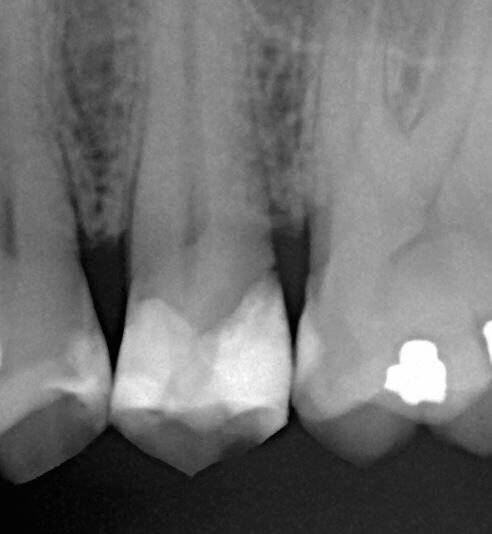

• Radiografía periapical: Permite obtener una vista detallada de un diente o una región, es decir, muestran la estructura completa de una pieza dental.